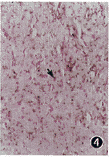

同样从以上19例鼻咽癌中选择10例进一步检测了cyclinD1 mRNA的表达。cyclinD1 mRNA集中于胞浆的一端,呈深浅、大小不一的紫蓝色斑点。6/10例鼻咽癌中等阳性(图4),4例弱阳性,1例鼻咽炎症上皮cyclinD1mRNA阴性。

图4 鼻咽癌中cyclinD1mRNA中等阳性表达。阳性染色(箭头所示)集中于胞浆的一端,呈深浅、大小不一的紫蓝色斑点。RNA原位杂交 ×400